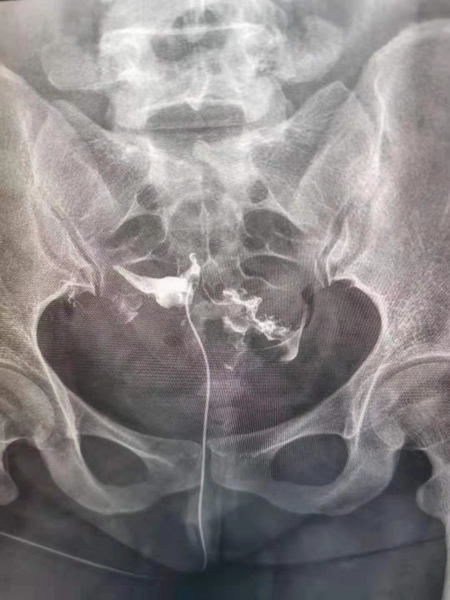

1.造影成像的圖像質量清晰直觀,臨床醫生可以通過讀片來判斷子宮輸卵管腔內的狀態,清晰的圖片對于炎癥、積水等異常診斷更為準確,降低了漏診率和誤診率,對下一步不孕癥的處理方向提高幫助。